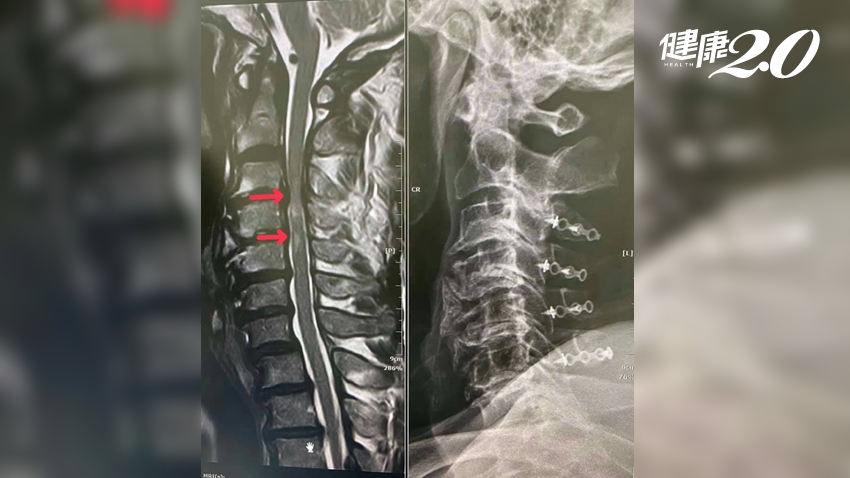

一位名38歲的電腦工程師,因為肩頸肌肉痠痛就診,檢查時讓醫師嚇一大跳,他的頸椎椎間盤全被壓扁嚴重退化,連60多歲的老阿伯可能都比他好,問診下來,除了曾出過車禍,研判造成頸椎退化的原因可能與他工作姿勢關係有關。